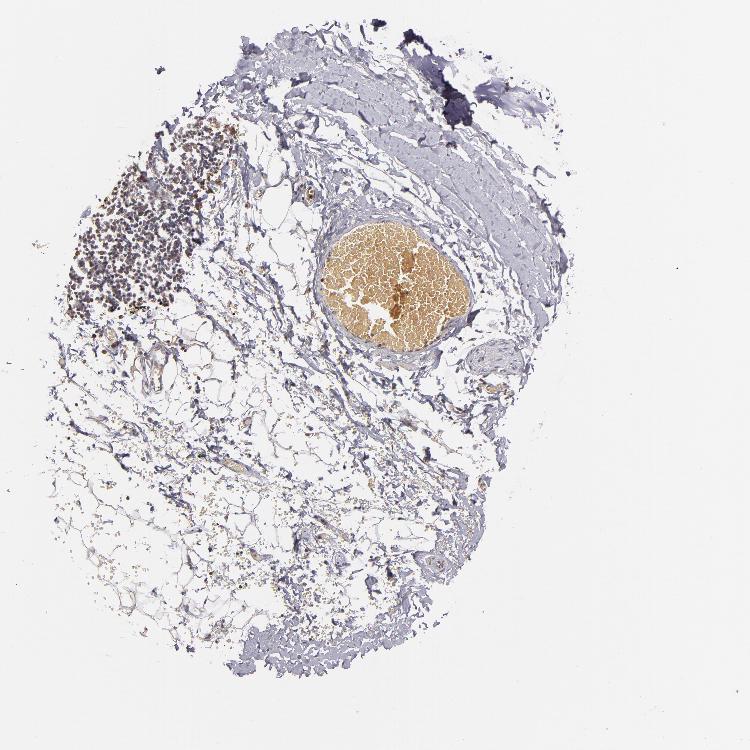

TISSUE PRIMARY DATA SOFT TISSUE Show tissue menu

SOFT TISSUE 1 - Antibody stainingi

Antibody staining in the annotated cell types in the current human tissue is reported as not detected, low, medium, or high, based on conventional immunohistochemistry profiling in selected tissues. This score is based on the combination of the staining intensity and fraction of stained cells.

Each image is clickable and will lead to virtual microscopy that enables deeper exploration of all samples and also displays staining intensity scores, fraction scores and subcellular localization as well as patient and tissue information for each sample.

Antibody HPA003056Antibody CAB002685

Fibroblasts MediumNot detected

Peripheral nerve LowNot detected

SOFT TISSUE 2 - Antibody stainingi

Fibroblasts LowNot detected